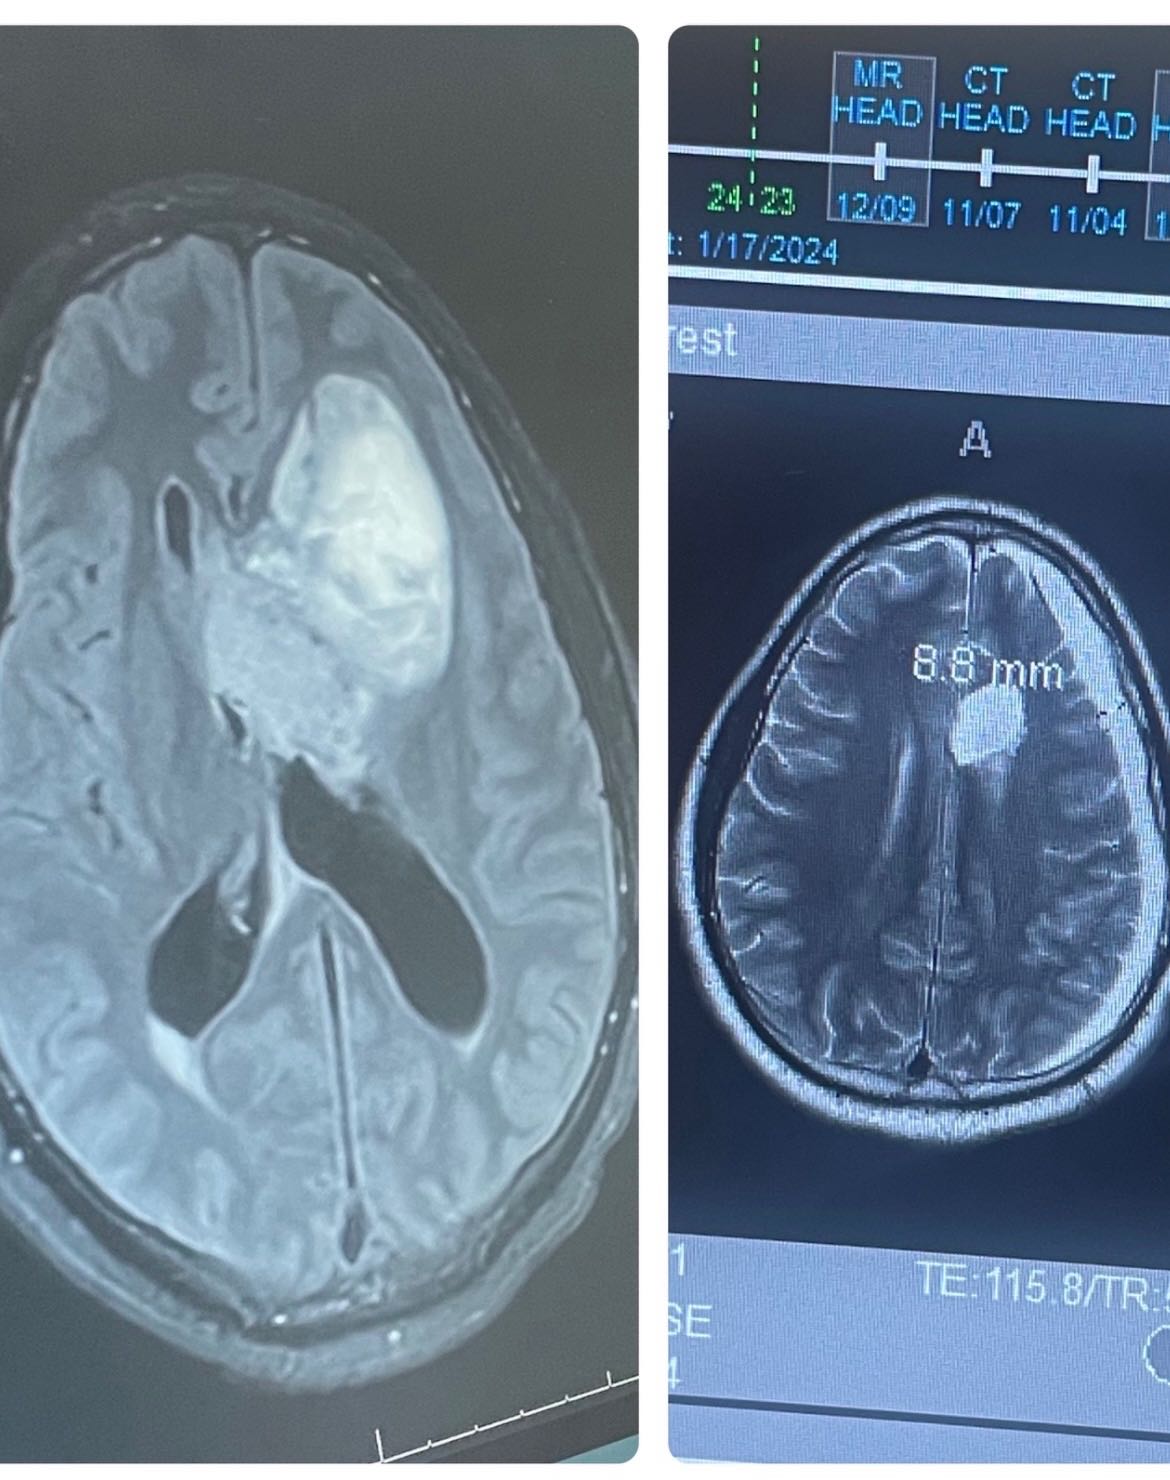

In 2016, I was in a terrible accident after the purchase of my new vehicle. It was at this particular time that I found out I had a brain tumor (Neurocytoma). I underwent surgery to remove it and was completely fine afterwards. I visited my neurosurgeon after my surgery, and things remained well. 2023 came, and my headaches began to recur severely. I made an emergency room visit where I was kept for immediate surgery to remove the Massive tumor pictured below.

Here we are in 2025, my tumor has returned, and I have to undergo another surgery for the (THIRD) time.